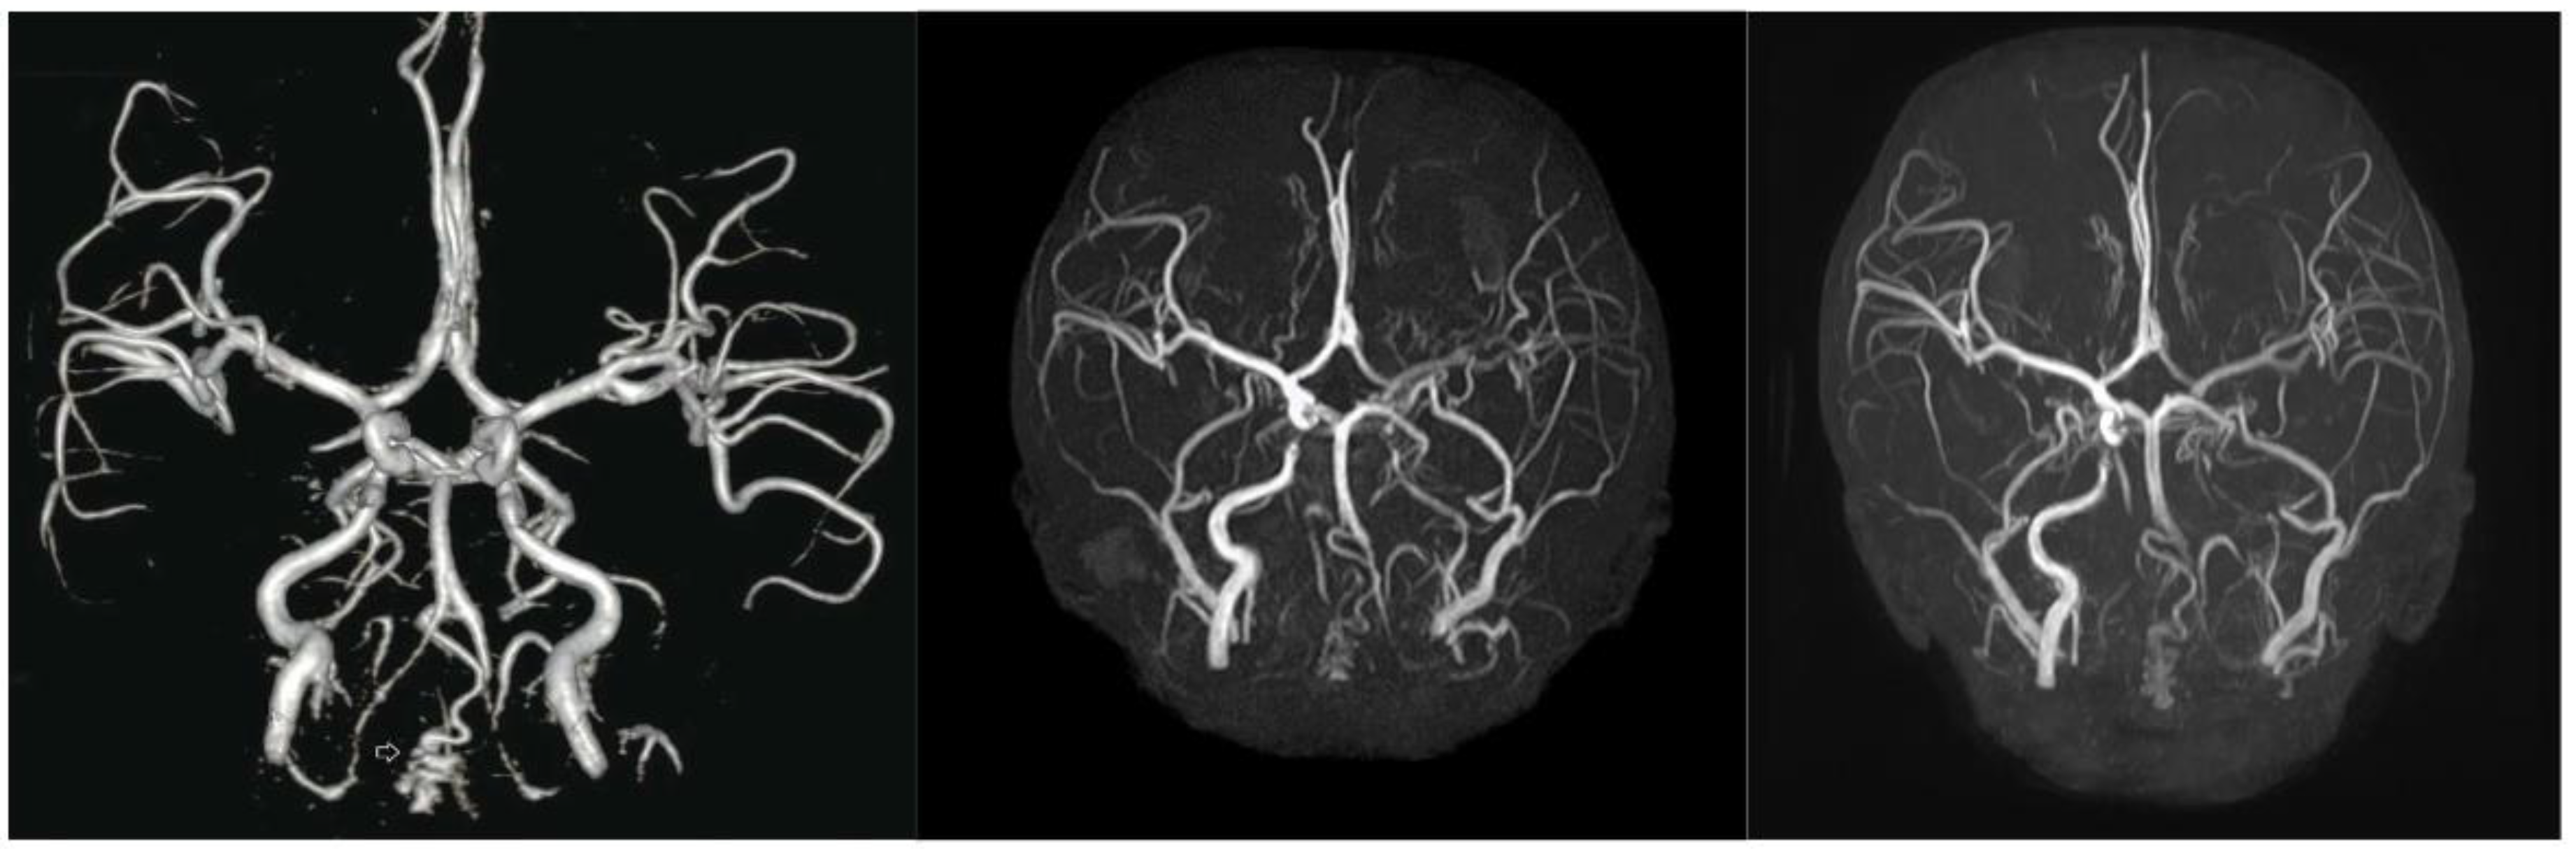

Despite treatment, atherosclerosis and cardiovascular deterioration did not stop or reverse. However, cerebrovascular deterioration shows a delayed progression. Two years before treatment, severe segmental stenosis of the bilateral vertebral arteries and mild stenosis of the bilateral ICA with collateral vessels were observed (Figure 2A). At baseline, vertebral artery stenosis progressed, and hypoplastic changes with segmental total occlusion in the left ICA were observed. Although the treatment did not completely halt vascular deterioration, no severe worsening was observed. (Figure 2C).

Figure 2. Changes in the cerebrovascular state before and after treatment were detected via brain magnetic resonance angiography (MRA). A) At diagnosis. Brain MRA revealed vertebral artery (VA) occlusion and a tortuous internal carotid artery (ICA) with collateral vessels. (B) At baseline. Diffuse hypoplastic changes with segmental total occlusion developed in the left ICA for two years before treatment, with sustained VA stenosis. (2C) At 5 months after treatment, treatment did not completely halt vascular deterioration, and no significant progression was observed.